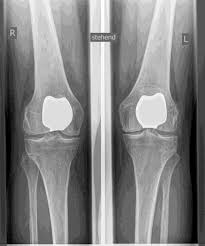

ERSATZ DES KNIESCHEIBEN GELENKES (PFJ)

Störungen der Beweglichkeit oder eine Instabilität sowie die Form der Kniescheibe (Dysplasie) können zu Knorpelschäden und Arthrose ISOLIERT IM patellofemoralen Gelenk führen. SIND DIE ANDEREN KOMPARTIMENTE ARTHROSEFREI, besteht die Möglichkeit eines

isolierten Teilgelenkersatzes des Kniescheiben-rückflächengelenkes.